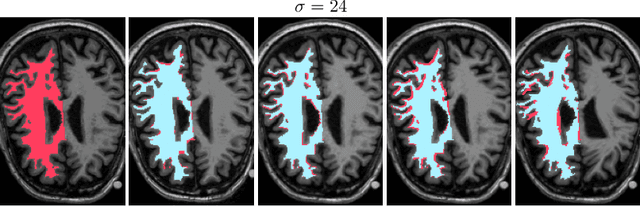

Abstract:We propose a new plug-and-play priors (PnP) based MR image reconstruction method that systematically enforces data consistency while also exploiting deep-learning priors. Our prior is specified through a convolutional neural network (CNN) trained without any artifact-free ground truth to remove undersampling artifacts from MR images. The results on reconstructing free-breathing MRI data into ten respiratory phases show that the method can form high-quality 4D images from severely undersampled measurements corresponding to acquisitions of about 1 and 2 minutes in length. The results also highlight the competitive performance of the method compared to several popular alternatives, including the TGV regularization and traditional UNet3D.